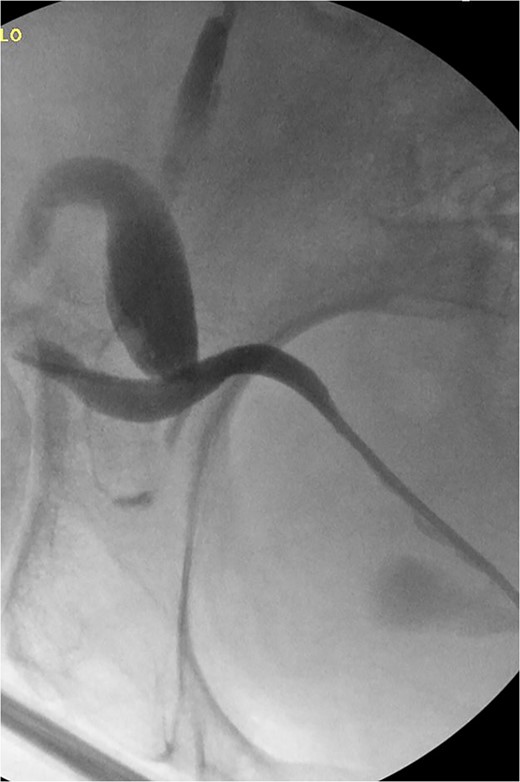

The patient was taken to the operative suite where he underwent cystoscopy, retrograde pyelogram and temporary ureteral stent placement (Fig. 2). Right inguinal exploration was performed, and the patient was found to have a large direct hernia containing abundant adipose tissue. The ureter and cord structures were identified. Adipose tissue was amputated with an energy device. The ureter was reduced into the retroperitoneum. The hernia was then repaired with modified Lichtenstein technique using macroporous polypropylene mesh. Retrograde pyelogram was repeated at completion of the hernia repair following stent removal. A serpiginous course of the ureter was noted without obstruction (Fig. 3). He was observed overnight and discharged home the following day. Post-operative course was uneventful.

Retrograde pyelogram exhibiting ureter herniated into scrotum prior to hernia repair. Filling defects consistent with air bubbles.